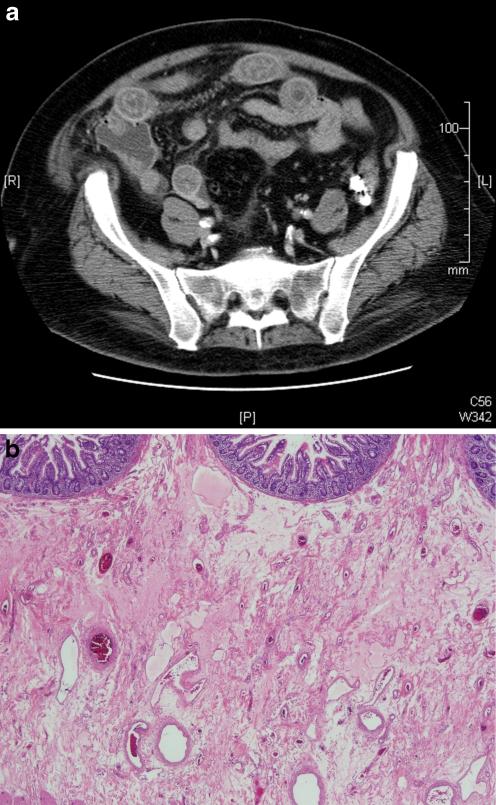

We describe a patient with known CLL who developed incapacitating, recurrent severe abdominal pains, culminating in partial bowel resection. Signs, symptoms, laboratory and pathologic findings demonstrated AAE.

我们描述了一位已知患有 CLL 的患者,他出现了使人虚弱的、反复发作的严重腹痛,最终导致部分肠切除术。体征、症状、实验室和病理发现均表明存在 AAE。